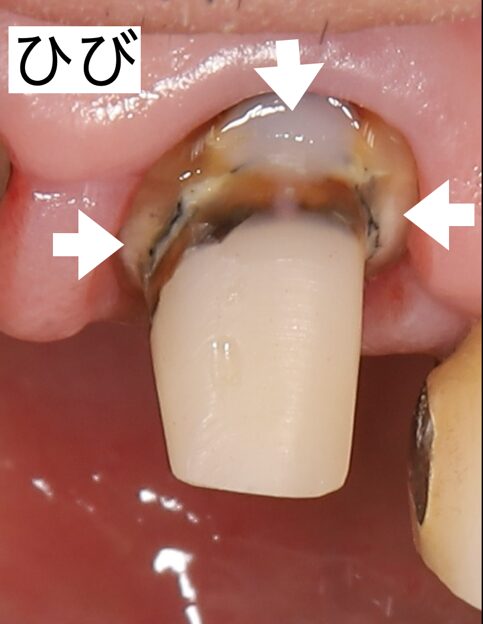

5年前に治療した歯がグラグラすると来院されました。この歯はもともと歯折線(ひび)が入っており、患者様には長持ちしない可能性があるとお伝えしていた歯でした。なんとか残して欲しいと患者様からの強い要望があり、結果的に5年ほどで、歯折してしまいました。患者様は先生のいうとおりだったねとおっしゃってくださいました。

では、なぜ無理にでもこの歯を残したかというと、この歯の下に埋伏過剰歯が埋まっており、そのままインプラントができなかったのです。それを摘出するには口腔外科にて摘出することになるからでした。今回はインプラント治療を希望されたので、まずは口腔外科にお手紙(対診)を送り、インプラント治療の件も伝え抜歯してもらいました。